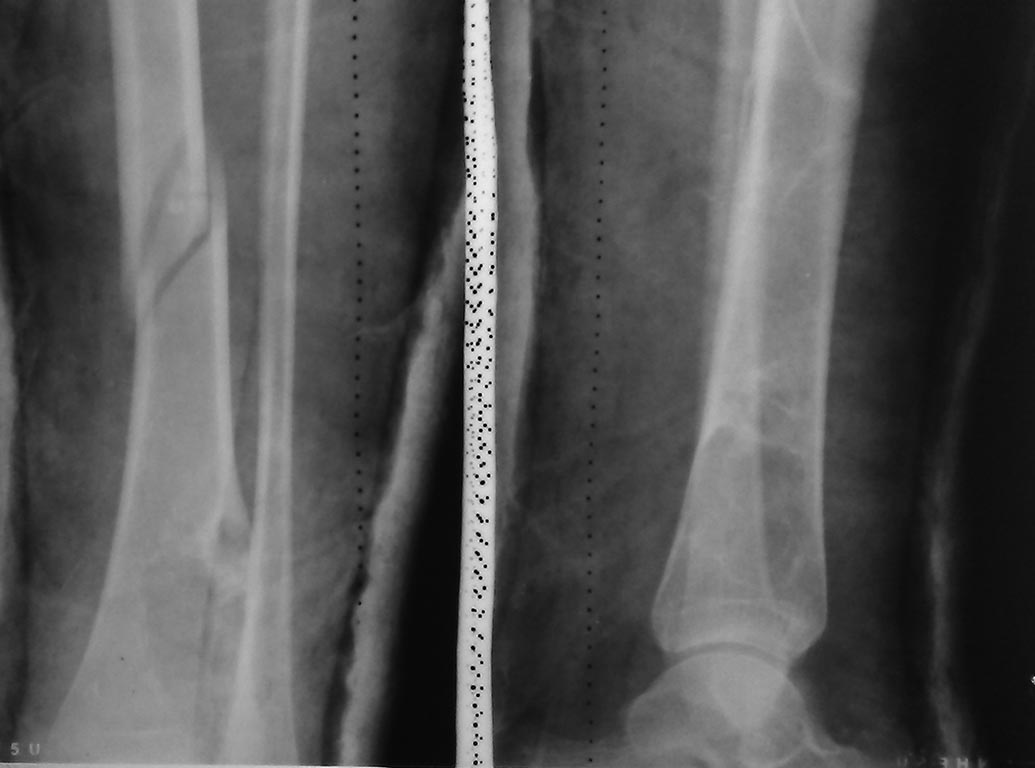

1. Снимок без гипса!!!

2 Снимок на протяжении с обеими смежными суставами в 2-х проекциях

Судя по всему перелом стабильный. Учитывая это, а так же юный возраст пациентки, было бы рационально ограничиться функциональной гипсовой повязкой (по Попсуйшапке А.К.)

Для лечения перелома подойдет любой из вариантов фиксации, включая консервативное, но решение принимается на основании рентген снимков с включением суставов. Гвоздь не желателен из-за возможного вовлечения опухолевого процесса!